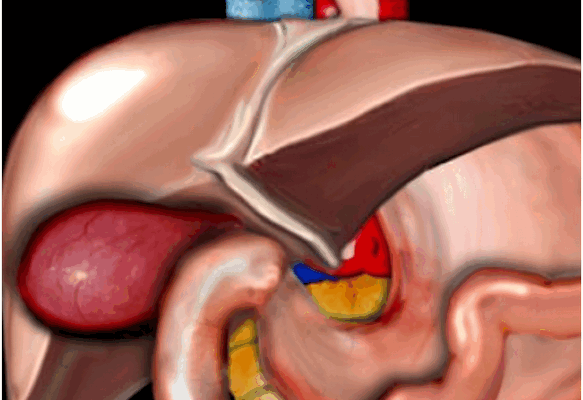

Схематичная патология. На данном рисунке продемонстрирован растянутый и гиперемичный желчный пузырь. Данные изменения встречаются при калькулезном холецистите, обусловленные обструкцией камнем желчного протока или шейки желчного пузыря.